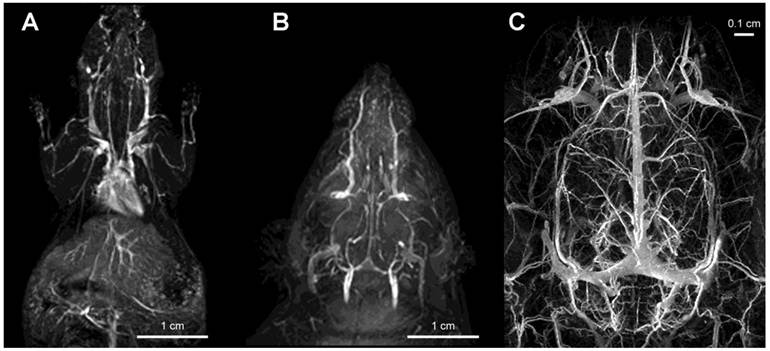

Figure 4

Imaging of vascular supply using PGC-DTPAGd. A- maximum intensity pixel (MIP) projection image of blood circulation in a mouse obtained using gradient-echo pulse sequence (1.5T, GRASS, TR/TE 60/8, FA 60, 2NEX, 8 cm field of view) after injecting PGC-DTPAGd at 25 µmol Gd/kg; B- a MIP image showing circulation in the head of a rat (imaging parameters similar to that of A); C - an improvement in imaging detail of rat cerebral circulation at 9.4T results from increased dose of PGC-DTPAGd (150 µmol Gd/kg) due to the lower molar relaxivity of Gd3+ at high magnetic fields. Adapted from [18, 103].

Gadolinium labeled PGC (PGC-DTPAGd) enables high-quality, high resolution images of blood vessel morphology [18], in rodents and rabbits [27] that can be obtained at various magnetic field strengths (1.5-9.4T), Fig. 4. After injecting PGC-DTPAGd, we were able to track arteriovenous circulation on the obtained images by using angiographic MR pulse sequences. Both the arteries and veins of small diameter (0.25-1 mm) became readily discernible for 3 h after the injection. We achieved a level of contrast equivalent to that achieved by the low mass contrast agent DTPAGd, but at a much lower dose of Gd (20 µmol PGC-DTPAGd versus 100-200 µmol DTPAGd). With the introduction of high field MRI (9.4T) much higher signal-to-noise images could be obtained by injecting approximately 0.15 mmol PGC-DTPAGd/kg (Fig 4). We further demonstrated the feasibility of PGC-DTPAGd assisted detection of slow gastrointestinal bleeding [28]. In the above model study we showed that at a dose of 35 μmol/kg PGC-DTPAGd we could clearly delineate small volumes of blood in the gastrointestinal (GI) tract (stomach and small intestine), whereas the same volume of Gd-free blood was not detectable. These results demonstrate that due to the long blood half life of PGC, blood pool imaging can potentially be helpful in detecting venous as well as arterial bleeding and in imaging intermittent GI bleeding over time.